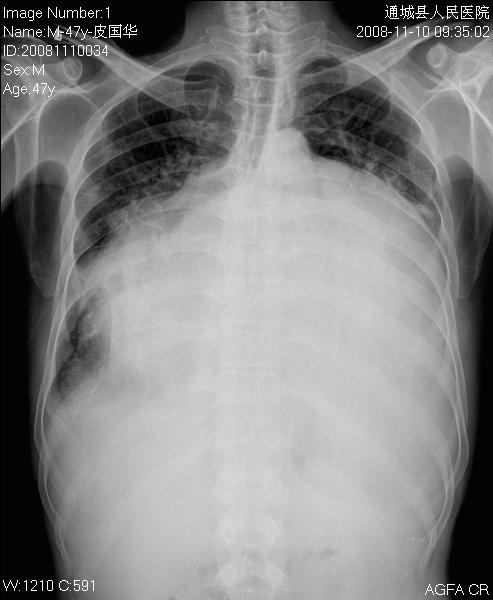

男性 47岁 自述风心病史十年 临床听诊-无 心超检查-无

平生第1次见如此大的心影。除了心影、隆突角大,右侧肋膈角钝外看不到其他征象。

好大一个心,心包内积液。

1)考虑风湿性心脏病,心包积液。2)双侧胸腔积液。建议行进一步检查。

曾进修时见一类似病例,当地医院以胸腔积液治疗抽到血性水,到上级医院彩超检查左房巨大,二尖瓣裂行瓣膜置换手术。

此病例考虑风心瓣膜病变及心包积液可能,还是彩超检查。

就单凭这张胸部正位片,我考虑风湿性心脏病,可能是一个双损合并有心包积液。

风湿性心脏病(累及多个瓣膜),合并心衰?心包积液?建议彩超检查。

该病例还是符合风心病改变的.但目前应是联合瓣膜病变.

心影大到这程度了,单一张正位咱就看不懂了,心包积液不能除外吧